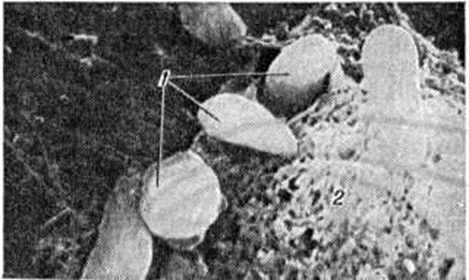

Специфических рентгенологическое признаков при Токсоплазмоз не бывает. Наиболее частым рентгенологическое проявлением Токсоплазмоз являются очаги обызвествления — петрификаты (смотри полный свод знаний) головного мозга, которые обнаруживаются на обзорных рентгенограммах черепа (смотри полный свод знаний: Краниография). Они, как правило, множественные, располагаются чаще в обоих полушариях, размеры их составляют от нескольких миллиметров до 1—1,5 сантиметров. Форма петрификатов округлая или неправильная (рисунок 4). Внутримозговые кальцификаты при Токсоплазмоз следует дифференцировать с очаговыми обызвествлениями другой этиологии, которые наблюдаются как у здоровых лиц (обызвествление шишковидного тела, твёрдой мозговой оболочки, сосудистых сплетений боковых желудочков мозга), так и при различных заболеваниях (туберкулезный менингит, обызвествленные гематомы, цистицеркоз и другие). Поэтому рентгенологическое симптоматика должна учитываться в комплексе с клиническими и серологическими данными. При острой форме Токсоплазмоз возможны поражения органов дыхания, которые выявляются рентгенологически в виде усиления лёгочного рисунка, очаговых и инфильтративных теней, выпота в плевральной полости, увеличения лимфатических, узлов корней легких. Специфического характера эти изменения не имеют.